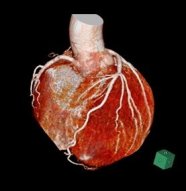

- 胸部

||||||

|

|||||

| 心臓CT | ||||||